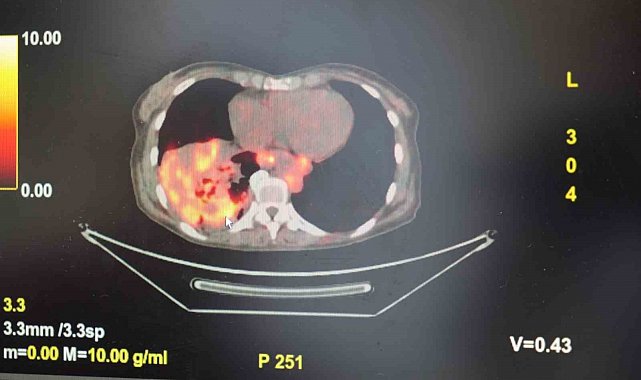

Dünyanın en prestijli tıp dergilerinden yayımlanan bir araştırma üzerinde açıklama yapan Prof. Dr. Şevket Özkaya, araştırmaya göre, sigara içmeyenlerde en sık görülen tür olan akciğer adenokarsinomu, kadınlarda akciğer kanserlerinin yaklaşık yüzde 60'ını oluşturduğunu söyledi. Prof. Dr. Özkaya, sigara dışındaki risk faktörlerinin başında radon gazının geldiğine dikkat çekerek, "Radon gazı, evlerimizde farkında olmadan soluduğumuz, renksiz, kokusuz, tatsız ve radyoaktif bir gazdır. Müsaade edilen değerlerin üzerinde solunduğunda akciğer kanseri riskini artırıyor. Radon gazı özellikle taş, toprak ve çimento gibi yapı malzemelerinde doğal olarak bulunuyor. Bu maddelerden ortama sürekli yayılan gaz, solunum yoluyla akciğerlere ulaşıyor" ifadelerini kullandı.